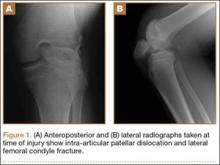

A 14-year-old boy presented to our institution after sustaining a direct blow to his left knee. The injury occurred as he jumped and landed on a flexed knee while playing with friends. The patient was unable to ambulate after the injury, and his left knee was locked in a slightly flexed position. Examination in the emergency department showed the knee to be held in approximately 60º of flexion, with an obvious bony prominence noted anteriorly over the femoral condyles. The patient was unable to perform a straight leg raise or any active range of motion (ROM) at the knee. Radiographs performed with the knee maintained in flexion confirmed that the patella was displaced into the knee joint and was rotated with the articular surface facing distally. Also noted was a coronal shear fracture of the lateral femoral condyle (Figures 1A, 1B).